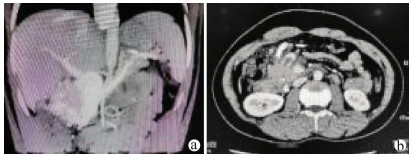

A case of decompensated liver cirrhosis complicated by abdominal necrotizing fasciitis

Guozhi WU, Xianglei ZHANG, Jia XU, Jinjun WANG, Wei LI

2021, 37(10): 2408-2410. DOI: 10.3969/j.issn.1001-5256.2021.10.030

Abstract(1184) HTML (302) PDF (2392KB)(73)

Abstract: